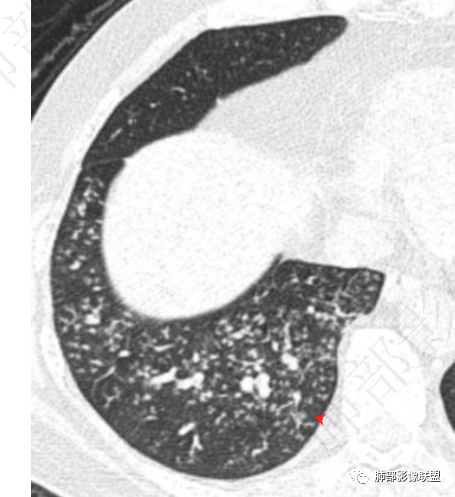

南边:急性、慢性,看树芽征的边缘。NTM也好,结核也好,他们属于慢性病变、反复发作,毒力不那么强,所以他相对来说发展速度非常慢,病变以增殖为主,因此他的边缘比较清楚,也可以引起支气管增厚。但是金葡菌是急性感染,所以他的边界是非常模糊的,外围磨玻璃非常多。

病变区支气管壁弥漫增厚,远端树芽征,周围GGO——渗出

4.金葡——小气道、肺泡,早期小叶性肺炎:树芽征、腺泡结节等

小气道树芽征、周围渗出——GGO

就是病灶因为炎性反应,渗出、增生,会融合。

小树芽——增大,与旁边的病灶融合,形成大病灶。再融合——再增大。金葡菌发展速度快,很快就是一个大病灶,呈叶段性改变。